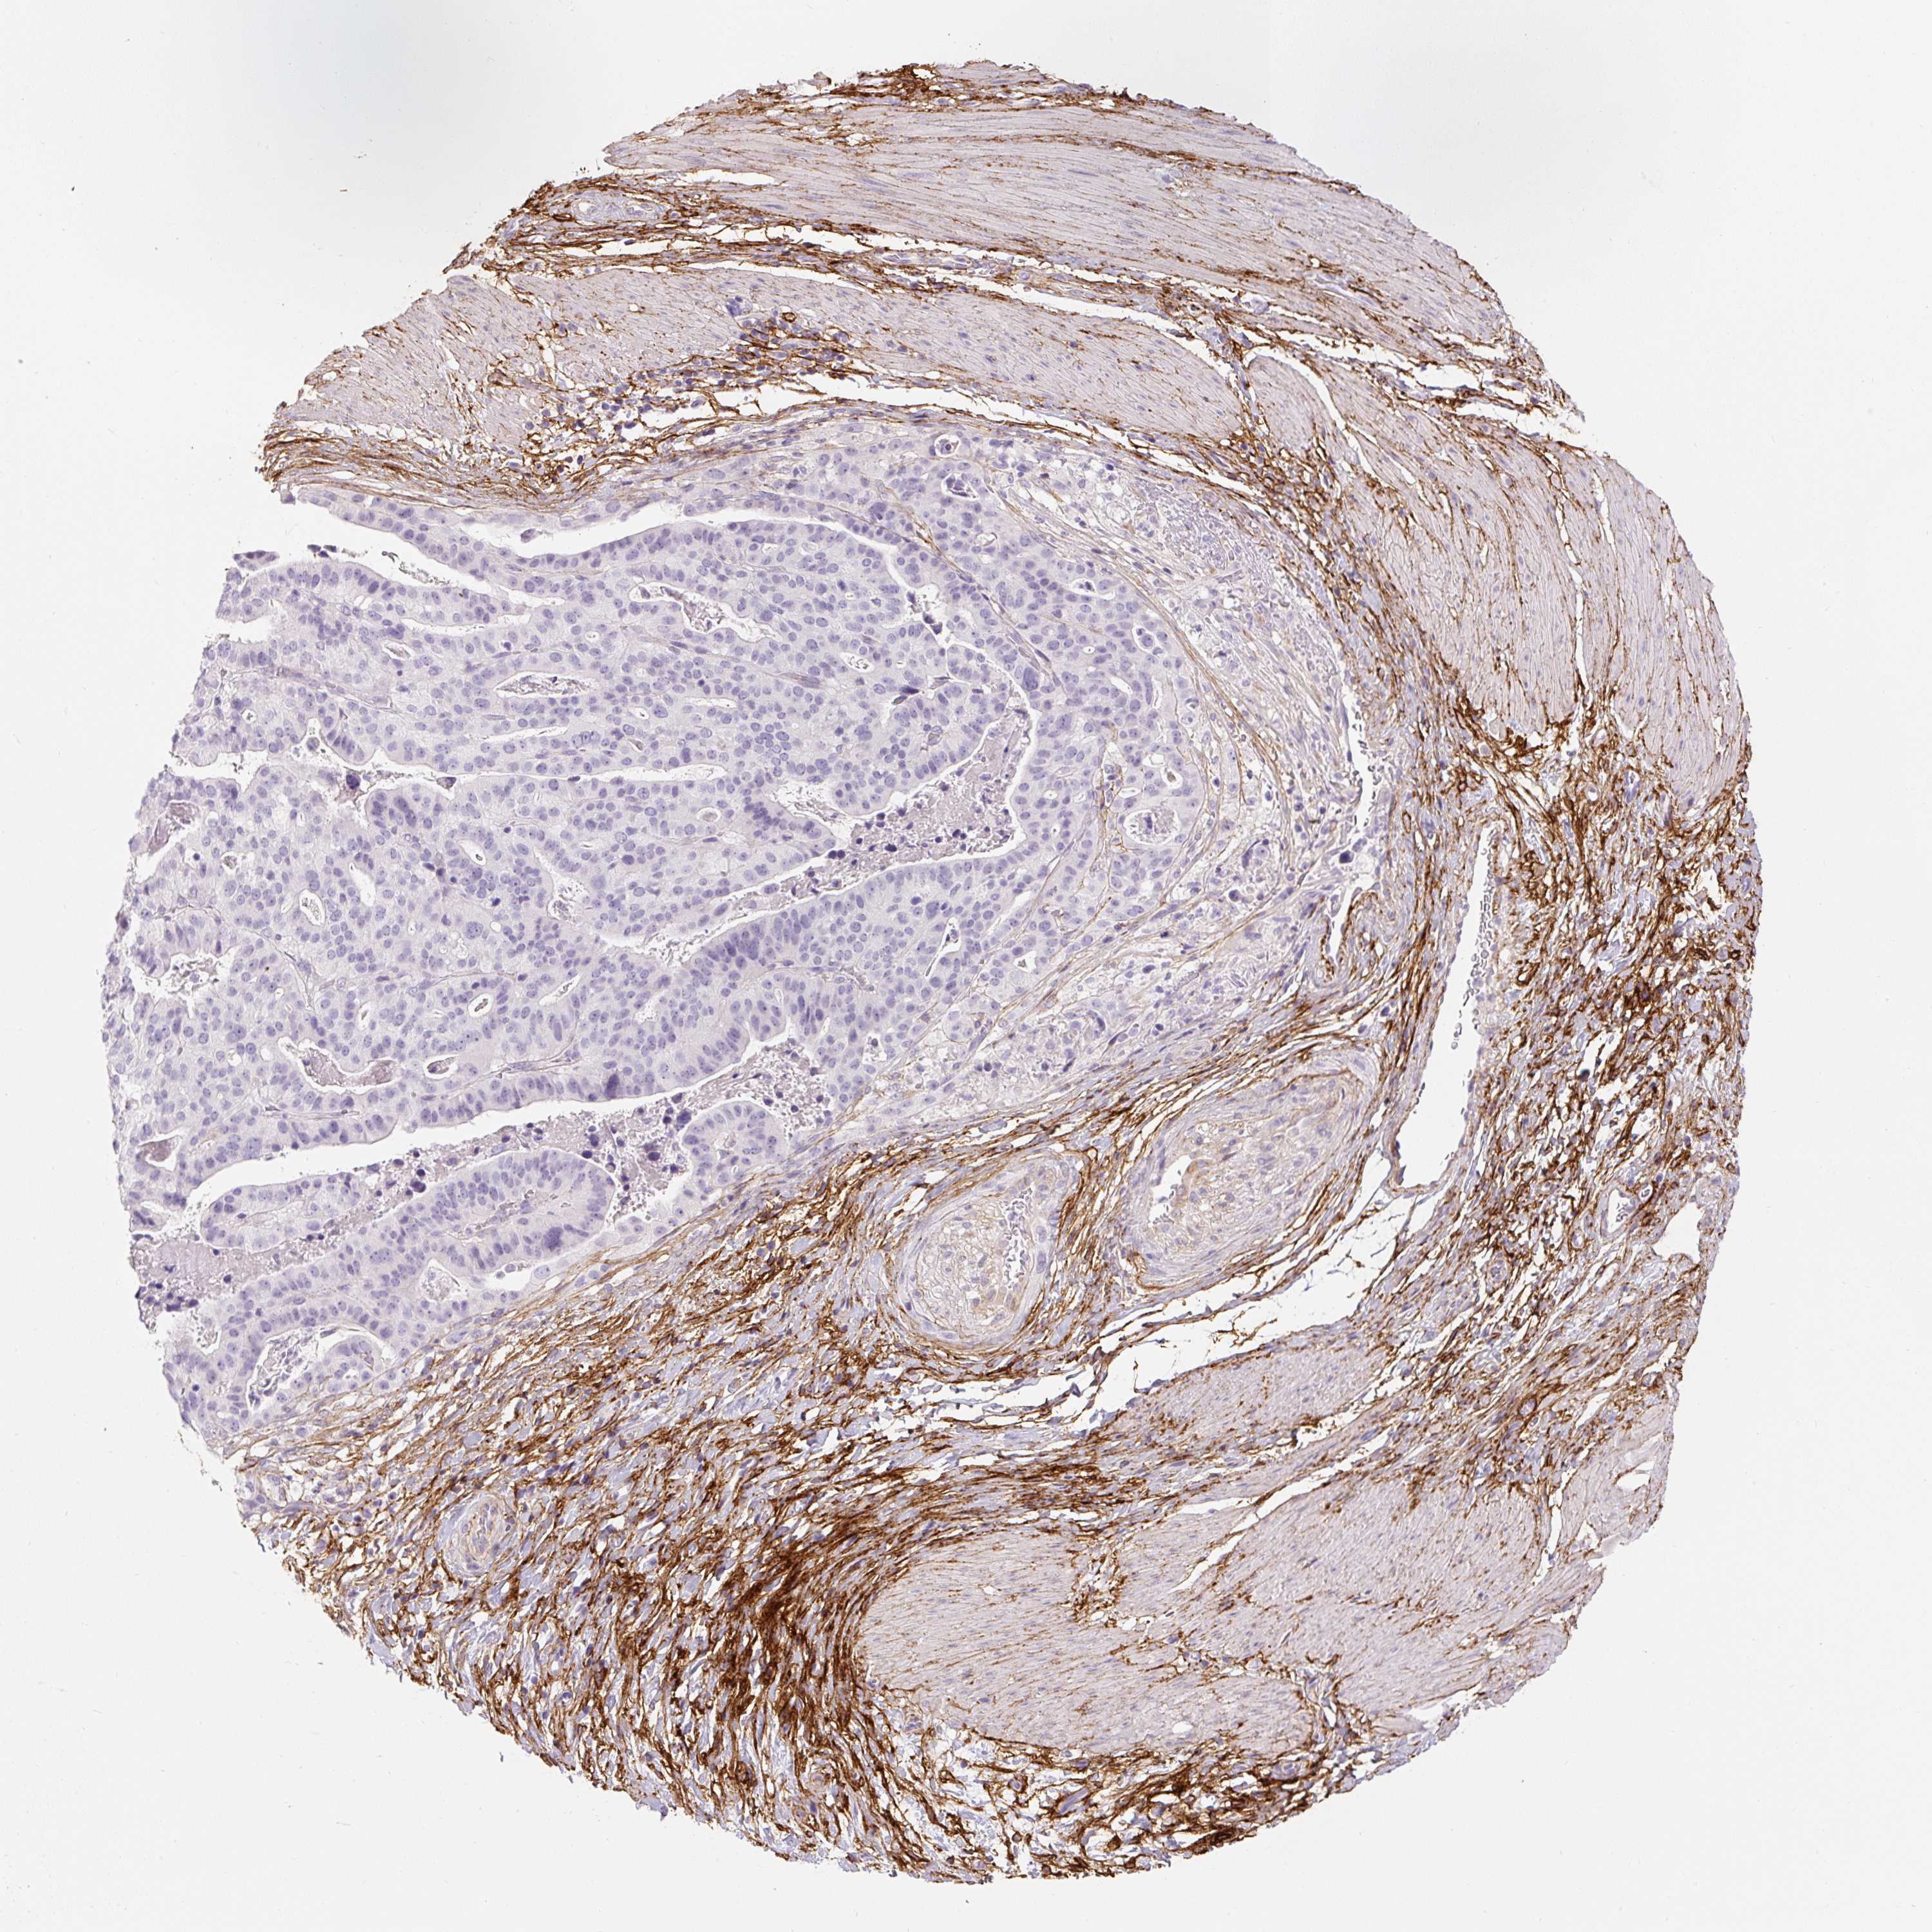

STOMACH CANCER - Protein expressioni

A mouse-over function shows sample information and annotation data. Click on an image to view it in a full screen mode. Samples can be filtered based on level of antibody staining by selecting one or several of the following categories: high, medium, low and not detected. The assay and annotation is described here.

Note that samples used for immunohistochemistry by the Human Protein Atlas do not correspond to samples in the TCGA dataset.

Antibody stainingi

Antibody staining in the annotated cell types in the current human tissue is reported as not detected, low, medium, or high, based on conventional immunohistochemistry profiling in selected tissues. This score is based on the combination of the staining intensity and fraction of stained cells.

Each image is clickable and will lead to virtual microscopy that enables deeper exploration of all samples and also displays staining intensity scores, fraction scores and subcellular localization as well as patient and tissue information for each sample.

HPA017759

HPA021057

CAB002670

CAB058696

CAB068188

CAB080202

Staining

High

Medium

Low

Not detected

Intensity

Strong

Moderate

Weak

Negative

Quantity

>75%

75%-25%

<25%

None

Location

Nuclear

Cytoplasmic/membranous

Cytoplasmic/membranous,nuclear

Adenocarcinoma, NOS

Adenocarcinoma, High grade